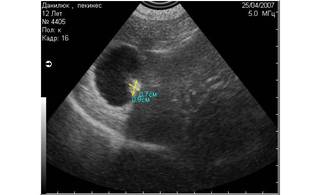

![]() |

Рис. 8. На снимке представлен гиперэхогенный объект в полости мочевого пузыря, испускающий эхоакустическую тень. На основании этого артефакта, мы можем предположить, что этот объект является конкрементом. |

Рис. 9. На снимке представлен похожий по величине и эхогенности объект в полости мочевого пузыря, не испускающий эхоакустической тени. На основании этого признака, мы можем предположить, что изучаемый объект является новообразованием. |